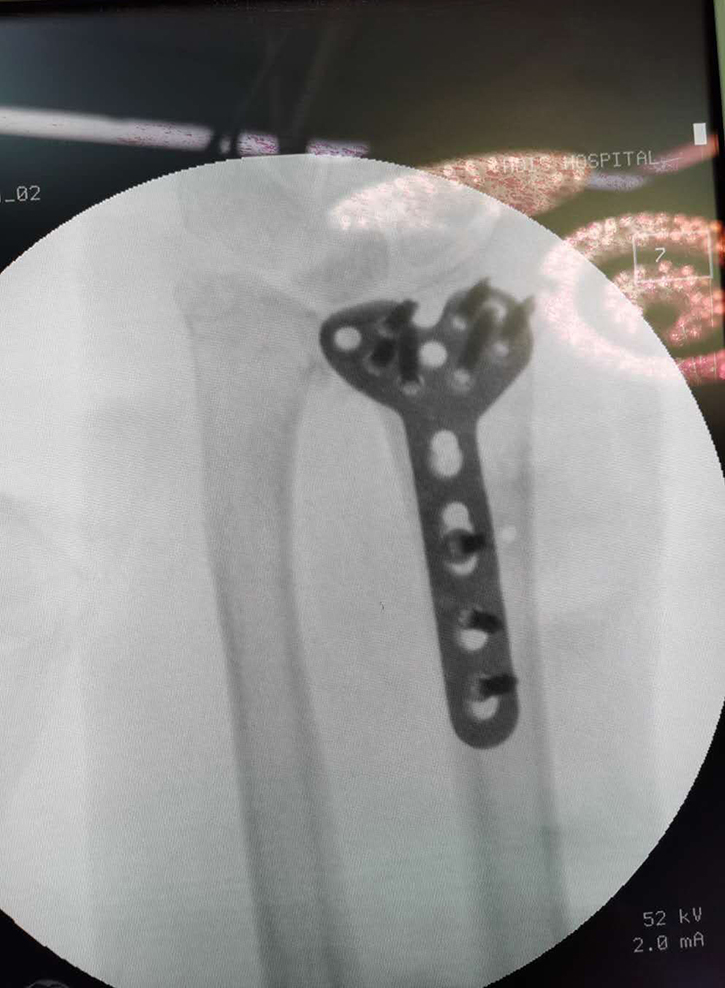

常州鼎健醫(yī)療器械有限公司、弘慈醫(yī)療集團(tuán)均屬于中信產(chǎn)業(yè)基金控股的醫(yī)療企業(yè),而鼎健醫(yī)療作為弘慈醫(yī)療重要戰(zhàn)略合作伙伴的骨科耗材供應(yīng)商,從弘慈醫(yī)療旗下弘慈醫(yī)院的臨床需求出發(fā),提供最適宜的骨科耗材產(chǎn)品和技術(shù)支持,助力弘慈醫(yī)療水平的持續(xù)提升。通過產(chǎn)業(yè)基金領(lǐng)導(dǎo)協(xié)調(diào)支持,供應(yīng)鏈的推動(dòng),達(dá)成強(qiáng)強(qiáng)聯(lián)手合作,6月22日,唐山弘慈醫(yī)院聯(lián)手鼎健團(tuán)隊(duì)首次合作開臺(tái)完成橈骨遠(yuǎn)端骨折鎖定鋼板置入手術(shù)。

這次手術(shù)由唐山弘慈醫(yī)院骨科主任宋曉明與鼎健團(tuán)隊(duì)于手術(shù)前共同討論手術(shù)方案,以鼎健新上市產(chǎn)品橈骨遠(yuǎn)端鎖定板為患者提供手術(shù)治療。宋曉明主任在手術(shù)結(jié)束后表示對(duì)鼎健醫(yī)療的骨科產(chǎn)品和技術(shù)給以高度肯定,患者也對(duì)這次的手術(shù)表示非常滿意。未來,鼎健醫(yī)療將繼續(xù)聯(lián)手弘慈醫(yī)療,積極應(yīng)對(duì)新常態(tài)下醫(yī)療格局新變化,為弘慈醫(yī)療提供領(lǐng)先的骨科產(chǎn)品和臨床解決方案。